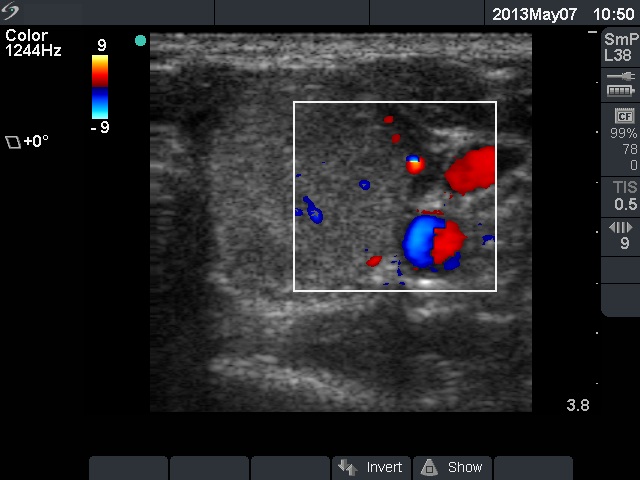

Ethanol sclerotherapy: non-toxic solid nodules - Case 5

Ten years after the therapy (ultrasonographic picture 6)

Left lobe, horizontal scan, color Doppler mode. The lesion presents signs of perinodular and intranodular blood flow, as well.